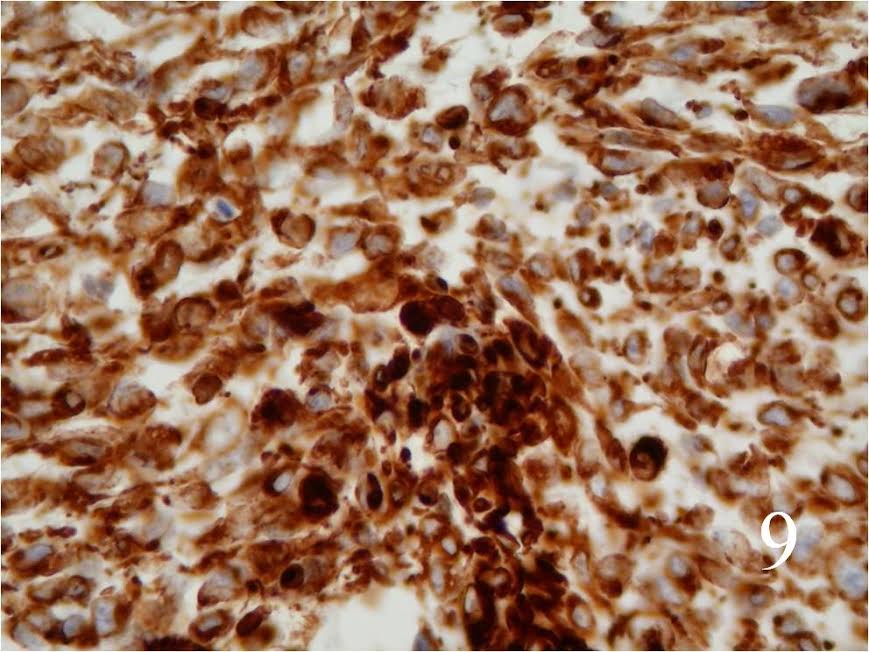

Immunohistochemistry

- S-100 protein positive (Fig. 9)

- Vimentin positive